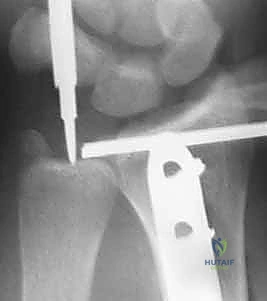

4. التثبيت الداخلي (Internal Fixation)

يتم استخدام شريحة معدنية قوية (Compression Plate) ومسامير لتثبيت العظم بقوة. هذه الشريحة تعمل كجسر يحمل العظم حتى يلتئم تماماً.

5. تقييم وتثبيت مفصل الكعبرة الزندي البعيد (DRUJ)

هذه هي الخطوة الأهم التي تميز الجراح الخبير. بعد تثبيت الكعبرة، يقوم الدكتور هطيف بفحص استقرار مفصل DRUJ.

* إذا كان المفصل مستقراً: لا حاجة لتدخل إضافي.

* إذا كان المفصل غير مستقر (يُخلع عند دوران الساعد): يتم تثبيته باستخدام أسلاك معدنية دقيقة (K-wires) تُترك لمدة 4 إلى 6 أسابيع، وقد يتطلب الأمر إصلاحاً مباشراً لأربطة TFCC الممزقة.